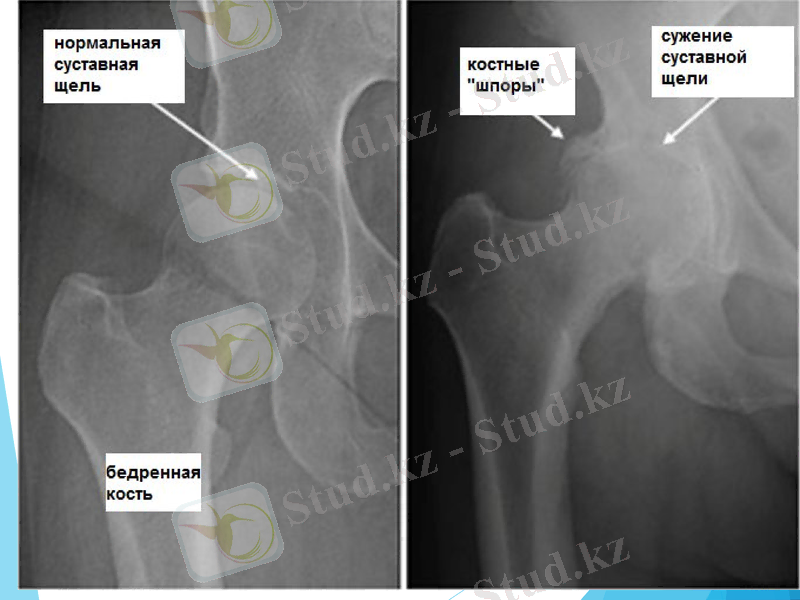

Жамбас сүйегінің туберкулезі (Коксит)

Коксит сүйек-буын туберкулезінің 20%- қамтиды.

3-7 жасар балаларда жиі кездеседі.

Туберкулезді интоксикация салдарынан бала әлсіреп, тез шаршайды, жамбас буынындағы ауырсыну тізеге де тарайды. Науқас ауырған аяқты жартылай бүгіп, салмақ түсірмеуге тырысады.

Рентгенографияда ортан жіліктің басында остеопороз, деструкция, буын саңылауның тарылуы көрінеді.